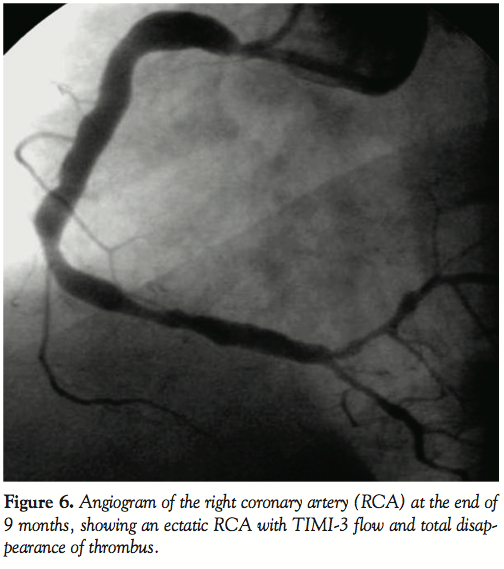

As there was normal antegrade flow with a residual thrombus burden in the ectatic distal RCA, the patient was put on oral anticoagulants maintaining an INR of around 2.5 (to prevent further thrombus formation), which was overlapped with intravenous heparin infusion (keeping the activated partial thromboplastin time > 50 seconds) with the hope that the endogenous fibrinolytic system would eventually dissolve the residual thrombus. The patient was kept under close clinical follow up. Though the patient was clinically asymptomatic, an angiogram at the end of the 9 months revealed the ectatic RCA with TIMI-3 flow and no evidence of thrombus (Figure 6).